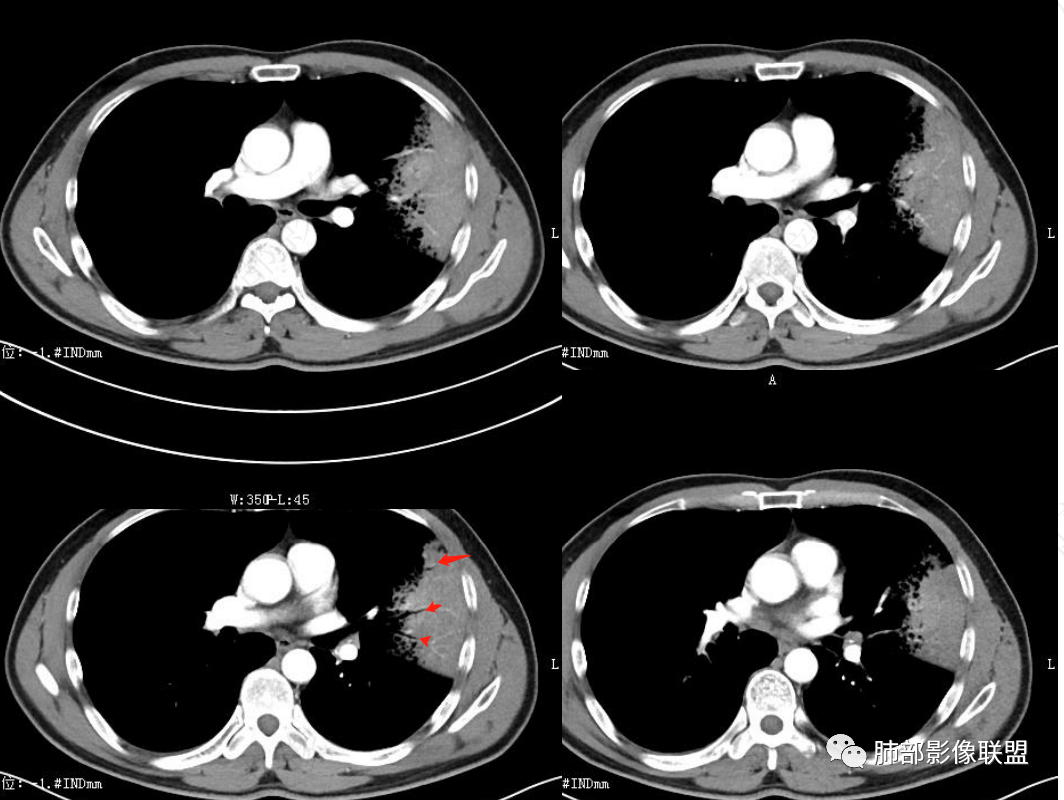

左肺上叶大片状实变影混合磨玻璃影,其内可见蜂窝征,增强扫描明显强化,进入病灶血管边缘有侵犯,结合病史,考虑肺炎型肺癌。鉴别诊断大叶性肺炎。

中年男性,咳嗽咳血,影像表现左肺上叶片状阴影,周围可见多发磨玻璃影,病灶内支气管僵硬,增强病灶内可见血管造影征,病灶与胸膜可见栽赃,考虑恶性病变,粘液性腺癌。

左肺上叶胸膜下实变伴周围边缘磨玻璃,其内可见枯枝征及蜂窝,不均匀强化,可见低密度影,血管显示尚可,考虑肺炎型肺腺癌

左肺上叶胸膜下大片状实变区,周围散在磨玻璃影,局部膨隆,界清,近端气管截断,叶间胸膜局部稍膨隆,增强扫描实变区轻度强化,内走形血管僵硬,轮廓毛糙,胸膜栽赃,半年病史考虑恶性,粘液性腺癌

左肺上叶大片状实变密度影,边缘见磨玻璃密度,呈外向内生长,内可见多发支气管影,走行僵直,增强后实变部分明显不均匀强化,血管纤细,考虑粘液腺癌可能大

男,46岁,反复咳嗽半年,痰中带血,加重10天,左肺上叶大片状实变影,边缘模糊,病灶内见蜂窝影及僵硬支气管,双肺内见多发小结节,增强扫描,病灶明显强化,左侧胸壁增厚,考虑恶性病变,粘液性腺癌可能。

左肺上叶片状实变,内可见多发空泡及蜂窝影,斜裂上方可见相同病灶由于斜裂阻挡呈重力分布,强化可见血管造影征,双肺弥漫分布气腔结节,临床咳白色粘液痰,考虑粘液腺癌

左上叶大片实变,实变以网格为中心,外向内生长,边界似清非清,实变内见枯树枝征及血管造影征,慢性病史,咳白色粘液痰,炎性标志物基本正常,定性恶性,考虑粘液腺癌

男,46,咳嗽半年,加重10天,白粘痰,偶有痰血。胸部CT:左肺上叶舌叶大片实变影,边缘GGO,长轴沿胸膜及叶裂展开,重力依赖,胸膜叶裂阻隔,内见蜂窝,钱币征,枯枝。强化不均匀,血管造影征。考虑粘液腺癌,鉴别大叶性肺炎、干酪性肺炎等。

2.左肺上叶大片状混合密度影,未见空洞,实变影主要位于胸膜下,长轴与胸膜平行,实变区内部密度不均、其内可见多发小斑片状低密度影,磨玻璃影多位居肺门一侧,可见网格,磨玻璃影边界多可分辨,重力分布趋势。病灶区支气管显示较为通畅,进入外围实变区渐至消隐。病灶轻度不均匀低强化,病灶区肺动脉显示较良好,未见破坏。